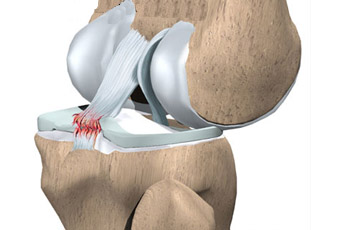

Knee replacement surgery is referred to as the surgical procedure that allows for replacing an arthritic or damaged knee with a metal, plastic, or ceramic device known as a prosthesis. This enables the patient to carry out movement similar to that of the healthy and natural knee. Although, the surgery can be performed to improve the conditions of the respective joint such as the ankle, wrist, shoulder, and elbow, knee and hip surgery are commonly performed joint replacement procedures. As the best orthopedic and joint replacement surgeon, Dr. B.R.Bagaria uses state-of-the-art techniques to help patients manage the various orthopedic disorders and knee-related problems. Moreover, patients with musculoskeletal and joint dysfunction or injuries are also provided quality treatment.

Knee replacement surgery is primarily recommended to patients who are aged 55 years or more and suffering from chronic pain conditions resulting in limited mobility of the patient. Knee replacement surgery or arthroplasty is one of the widely performed surgeries to overcome the pain caused by knee joints damaged due to arthritis, any trauma injury, etc. The outcome of the surgery can be observed in terms of enhanced mobility of the joint. The surgery may cost around Rs. 1,50,000. But it might change depending on a number of factors such as the cost of the knee implant, the hospital charges, and the fee charged by the joint replacement surgeon, the expertise of the surgeon, and the technique used for the surgery.

KNOW MOREA tear in the ACL ligament can cause major injury in the knee and you need to consult the best ACL doctor in Jaipur. The knee joint is formed by the three bony structures called the femur, the tibia, and the patella. The Anterior Cruciate Ligament (ACL) is known to be the main ligaments in the knee that connect the femur to the tibia and is one of the commonly injured ligaments of the knee.